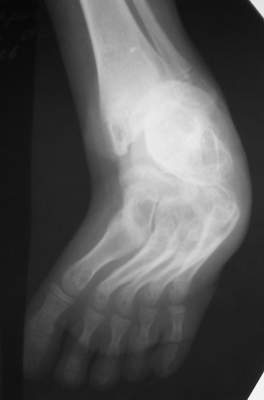

Уважаемые коллеги,Ребенок, мальчик, 11 лет...Врожденная косолапость,до 4 лет лечился консервативно, в 4 года оперирован у нас - операция по типу Зацепина, далее аппаратИлизарова...Предоперционная картина - как на рис "case 1 a" (фото другогобольного)...При операции использовался аппарат с "моноблоком" стопы -см. "case 1 b" (фото другого больного) -в связи с чем интраоперационно провели достаточно выраженную одномоментнуюкоррекциюпосле чего возник некроз в областиоперационных ран в результате чего "вывалился" "кусок" по внутреннейповерхностих...аппарат сняли... больного перевели в отделениемикрохирургии... с другой голени делали пересадку... прижилось...больного выписали...все это было 7 лет назад...3 года назад больной лечился в Астрахани...Никаких выписок нет (не видел...)(хэллоу, астраханцы!!! если есть - отзовитесь...),но со слов мальчика и его матери ему делали удлинение на уровневерхней трети голени плюс исправляли стопу... опять-таки со слов -сразу же после коррекции стопу загипсовали на 6 нед, после чегопрописали ночные тутора плюс ортообувь... т.е. после коррекции стопу ваппарате не выдерживали и гипсовали всего 1,5 мес.... через 6 месстопа "ушла" в исходное положение...с которой он пришел к нам сейчас... (case 2-9)В настоящее время у мальчика эквино (!!!)-варус... в подтаранномсуставе полный анкилоз... (см. Ro)Были предложения исправить деформацию аппаратно с остеотомией черезладью...Передумали:-)...Лично у меня возникают также вопросы на счет плюсне-клиновидныхсусутавов... и так я их Ro-фировал, и эдак (снимки не представлены), авсе равно не могу избавиться от впечталения, что и в них имеется некоефиброзно-костное анкилозирование...А на КТ у больных денег нету...Короче...Наложили аппарат...Попытаемся растянуть стопу + "подкоррегировать" варус иубрать эквинус...А после этого определиться с уровнем остеотомии (это официальноемнение...)Я же хочу сделать все тоже, за исключением остеотомии (при условии чтонет того самого анкилозирования на уровне плюсне-клиновидныхсусутавов...)Убрать варус и эквинус на фоне удлинения...коррекция с гипер-...плюс подержать в этом положении 1-1,5 мес...Но не лежит рука к остеотомии...Единственное, после коррекции есть желание "отсепарировать" подошвенные связки с костной "основой" от пяточной кости и загипсовать в таком положении во избежание возможного рецидива...А там посмотрим...мнения ???